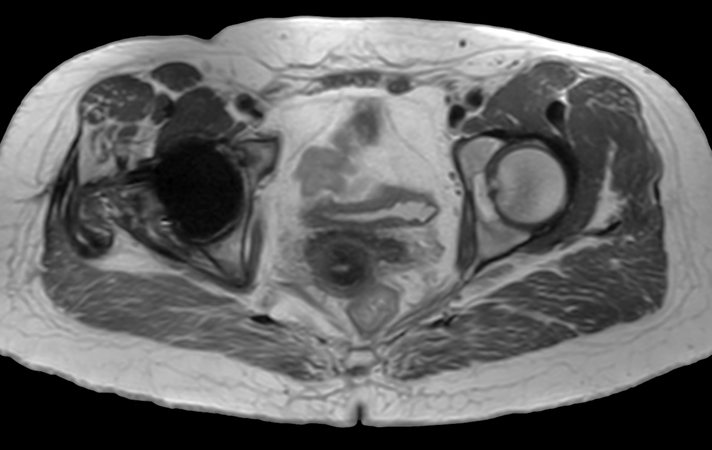

Hip imaging with metal implant

Used Solution

**Only for use with MR Safe or MR Conditional Implants by strictly following the Instructions for Use.